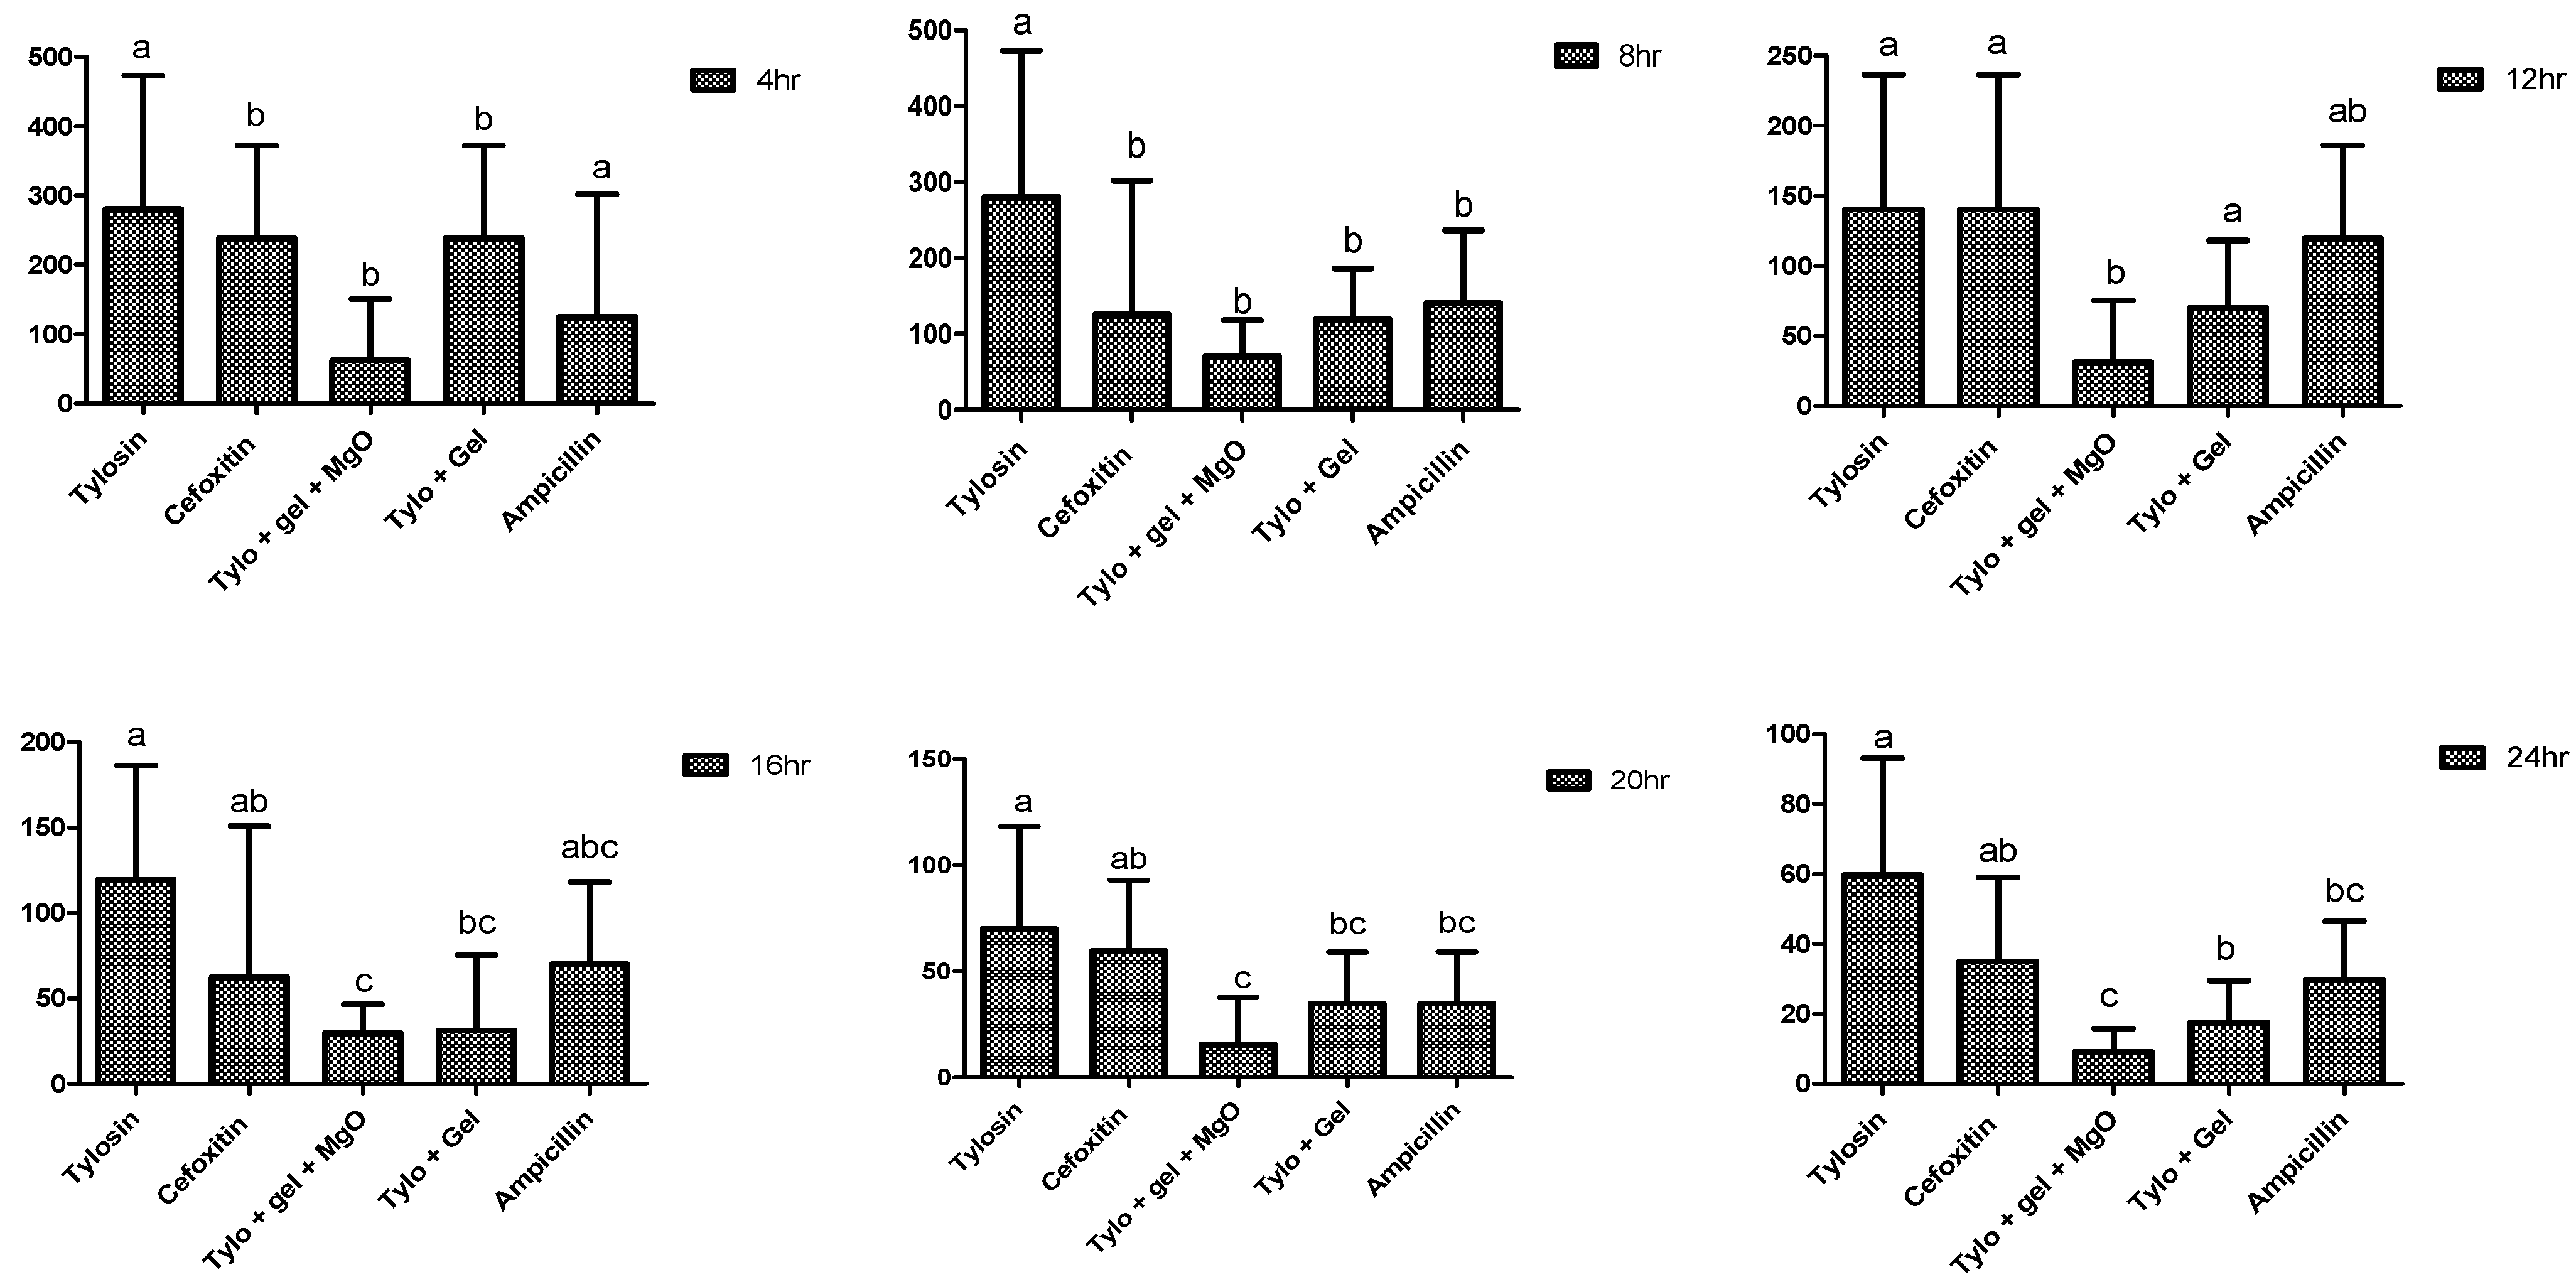

2.4. Antibacterial Potential of Gel-Based Nanoparticles and Antibiotics

4.7.1. Well Diffusion Assay

4.7.2. Minimum Inhibitory Concentration